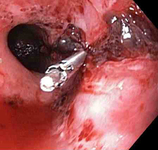

Mallory Weiss tear after application of through-the-scope clip results in haemostasis

From the personal collection of Douglas Adler; used with permission